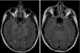

Familial occipital calcification and epilepsy